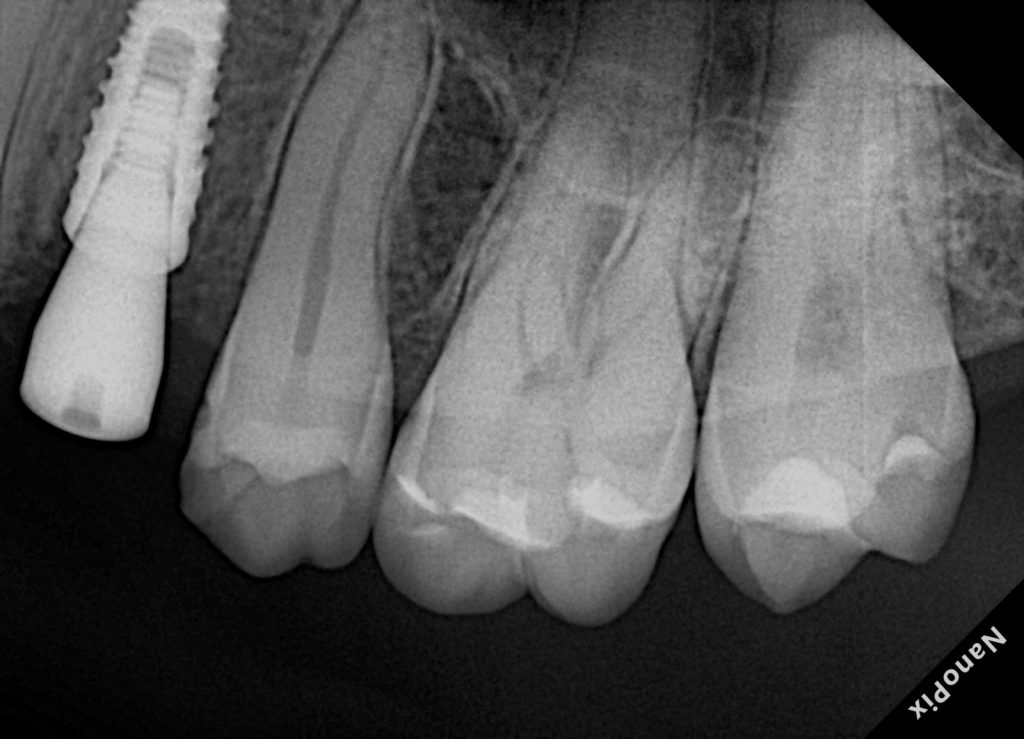

9) Radiographic verification

Step 19: Post-op bitewing/periapical

Assess:

- No overhangs

- Proper marginal seal

- Anatomical contour

- Contact area (indirect sign: no obvious open contact + correct contour)

Images to place

- Fig. 14: Post-op radiograph.